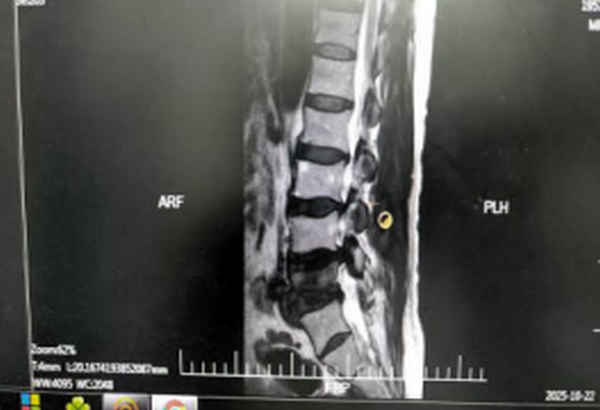

齐医附属二院骨外三病区病人马大爷,2个月前出现腰部疼痛及左侧下肢麻木症状,当时未重视,未经性系统治疗。近期症状加重,休息后症状不缓解,疼痛症状导致马大爷无法像正常人一样平躺,只能坐着睡觉,使得马大爷苦不堪言,通过多方介绍,联系到齐齐哈尔医学院附属第二医院骨外三病区刘艳楠副主任医师,刘主任看到病人后,进行查体,完善相关检查,MR示:腰椎间盘突出伴椎管狭窄。

马大爷就诊时跟我说:“医生,我已经整整一个月没法平躺下睡觉了。” 大家可能觉得这很平常,但对于一位因严重腰椎间盘突出导致神经根性疼痛的患者来说,“无法平卧”意味着他最基本的休息权利都被疾病剥夺了。他描述了一种典型的“被迫体位”:任何尝试平卧的动作,都会引发向下肢的放射性电击样剧痛。这迫使他在夜间只能保持半卧或坐位,身心俱疲。经过详细的体格检查和影像学评估,我们明确了病因:腰椎间盘突出物,如同一个“关键的楔子”,牢牢地压迫了神经根。当患者平卧时,椎管内压力发生改变,这种压迫会加剧,从而引发剧烈症状。这完美地解释了为什么他“不能平卧”。